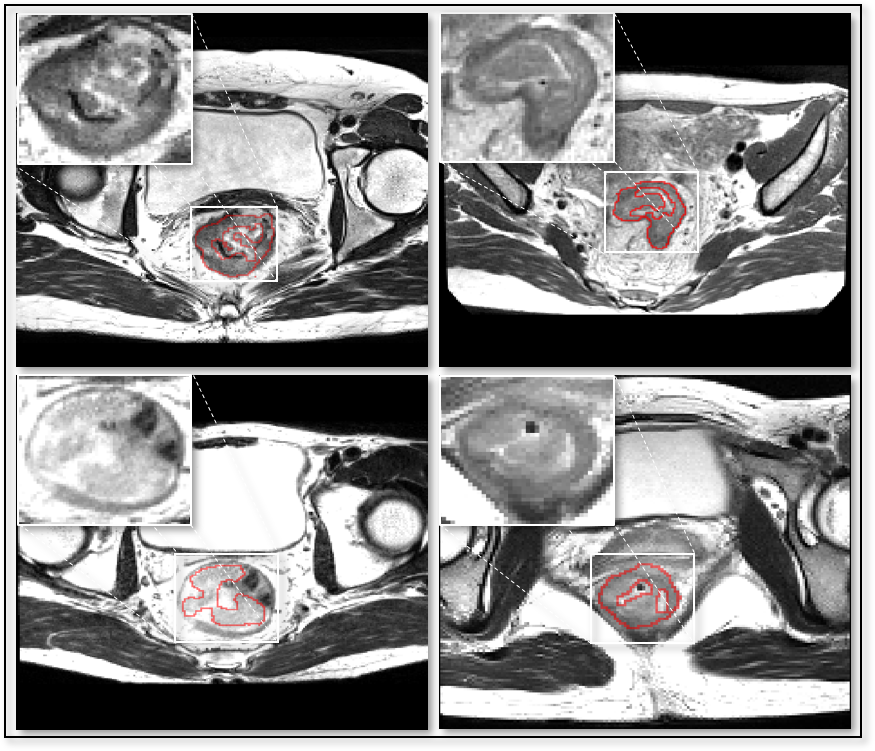

Refer to caption

Figure 1: Typical examples of MR slices with colorectal cancer. The cancer regions are delineated with red lines and zoomed in for clear illustration. Clearly, the target areas cannot be well separated by intensity clipping, shape models or positional priors.

Such demand defines a task of automatic detection and segmentation of the targets from whole 3D image volumes. Compared to processing manually selected RoI patches, the superiority of being fully automatic simplifies the workflow, excludes manual intervention and enables fast processing of large amounts of image volumes. Taking initial works based on super-voxel clustering [3, 4] one step further, deep learning based methods dominate the state-of-the-art of detection and segmentation field. However, deep learning based methods for this task are challenged by following factors: weak intensity specificity, absence of shape characteristic, lacking positional priors (as is illustrated in Fig. 1), class imbalance and long processing time of existing methodologies under inferior GPU or CPU-only deployment environments.